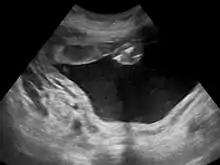

Polihidrâmnio (ou polidrâmnio) é uma condição médica na qual há excesso de líquido amniótico no saco amniótico. Essa alteração acontece em 1% das gravidezes, e é tipicamente diagnosticada quando o índice de líquido amniótico é superior a 24 cm.[1]